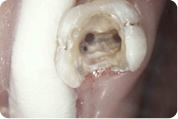

Slijedeći korak je prikazivanje endodontskog prostora tj. "otvaranje zuba" tijekom kojeg doktor dentalne medicine uklanja ostatke upaljenog ili nekrotičnog tkiva i pronalazi korijenske kanale. Ukoliko je pulpa vitalna, tj. živa, područje se prethodno anestezira jer je zahvat u protivnom jako bolan. Potom slijedi instrumentacija korijenskih kanala pri čemu doktor dentalne medicine tankim iglicama ulazi u kanale. Njima se uklanjaju ostatci tkiva i detritusa, čiste i šire korijenski kanali po pravilima struke.

Kanal se širi iz razloga da se olakša uklanjanje nepoželjnog sadržaja te da se isti može hermetički napuniti. Kad je kanal pripremljen, puni se gumastim materijalom ( štapićima ) i cementom.